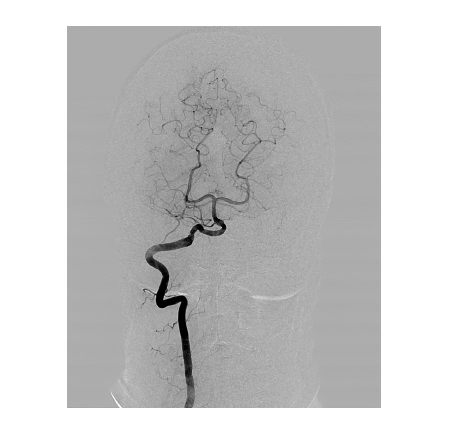

The high image quality provided by mobile C-arm systems is achieved due to a digital imaging system, which allows seeing even the smallest defects and pathologies. A mobile C-arm system model with a flat panel detector provides for imaging of even the smallest vessels. The modes of pulsed fluoroscopy, lowered dose fluoroscopy, and special quality fluoroscopy in combination with the wide APR program range, which considers the patient’s age and the body build, allows obtaining a high-quality image with the minimum exposure dose.